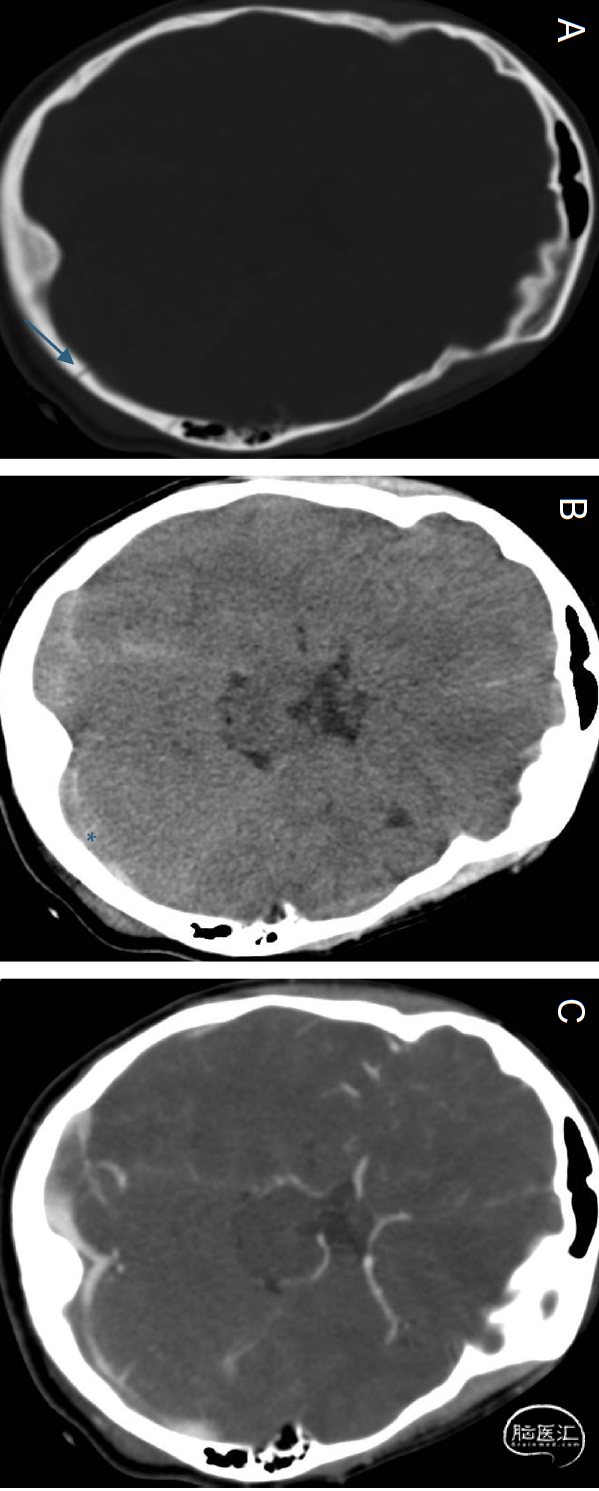

图3(A)轴位CT(骨窗)显示左枕骨骨折横跨横窦(箭头所示)。(B)轴位CT(软组织窗)可见左枕部硬膜外血肿(星号标记)压迫横窦。(C)轴位CTV:初始报告怀疑骨折部位上方存在脑静脉窦血栓。经回顾性复核,实无真实血栓存在;血肿压迫模拟血栓表现。本案例揭示了重要诊断误区:硬膜外血肿的外在性窦腔压迫可模拟血栓形成。经资深专家重新评估排除脑静脉窦血栓诊断: